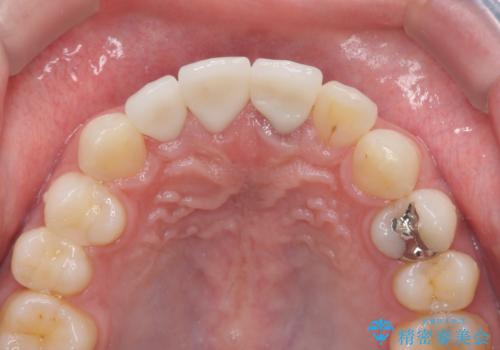

・歯の変色 →ジルコニアクラウンの製作

歯の挺出を行ったことで歯ぐきの腫れも改善され、安定した歯周環境下でのセラミッククラウン治療を行うことができました。